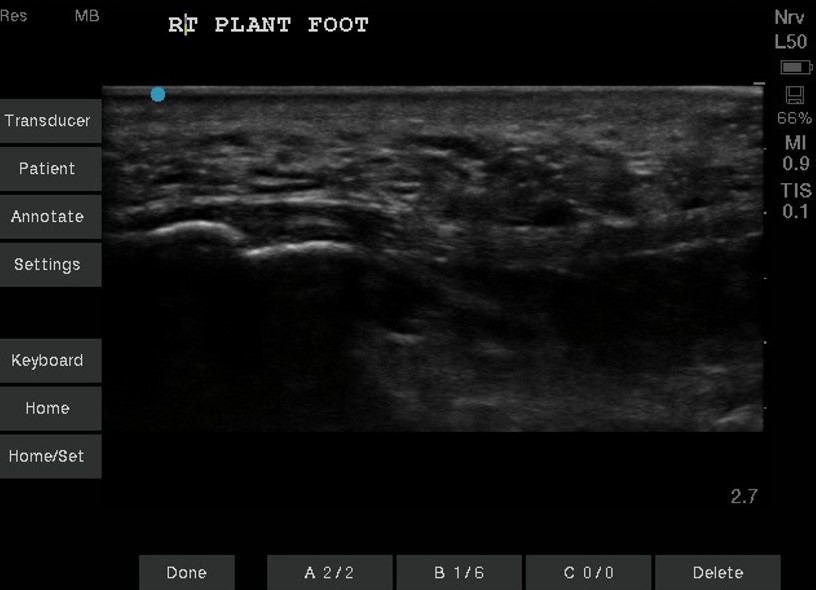

Unlabeled right plantar foot in long axis.